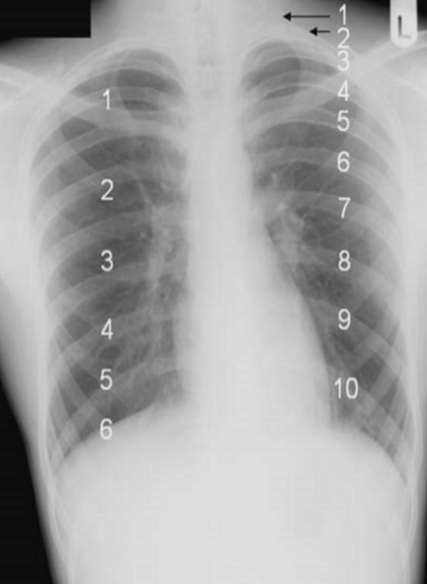

trachea divaiated to the right due to rotation.

distance between clavical and spinuss process not equal on both sides. rotated to the left.

Left hilum higher than right (NL)